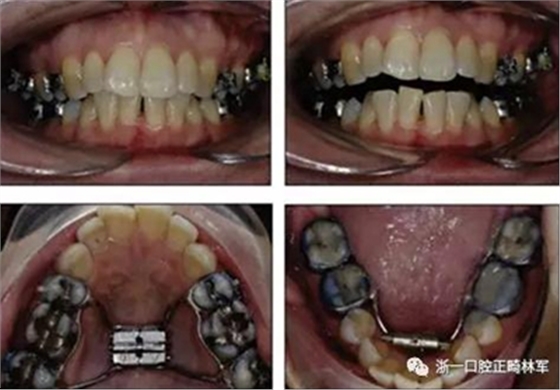

術(shù)后第9天開始旋轉(zhuǎn)擴弓器,每天轉(zhuǎn)2次,每次轉(zhuǎn)90度,即擴開0.5mm。每隔1周進行檢查,目標上頜擴開9mm,下頜擴開6mm。18天后,上頜中切牙間出現(xiàn)8mm間隙。下頜出現(xiàn)6mm間隙,(于13天出現(xiàn)后,停止旋轉(zhuǎn)擴弓器)。在擴弓器旋轉(zhuǎn)3天后,拍片發(fā)現(xiàn)左下頜中切牙遠中牙根中段有一條低密度陰影,臨床冷熱診反應(yīng)遲鈍,可能為術(shù)中損傷所致。牙體牙髓科會診,建議行根管治療,故行根管治療。

擴弓保持8周后,除擴弓器影響牙外粘接托槽,使用0.014鎳鈦絲進行排齊、整平。旋轉(zhuǎn)停止后3個月拆除擴弓器,全口粘接托槽,使用0.016niti繼續(xù)排齊整平。佩戴可摘保持器,保持上頜寬度。在使用至0.018x0.018niti7周,徹底排齊整平后,使用大弓型的0.016x0.022不銹鋼絲,繼續(xù)維持原有寬度,同時停止使用可摘保持器。掛II類牽,糾正磨牙關(guān)系,使用鏈圈關(guān)閉散在間隙,少量使用IPR去除局部前牙的黑三角。術(shù)后9個月拍全景示,牙根平行度可,再無其他牙根出現(xiàn)問題。1年7個月后治療結(jié)束。上下頜3-3舌側(cè)保持器+哈雷氏保持器進行保持。